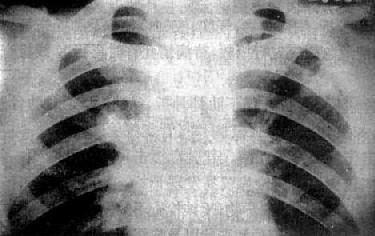

粟粒型肺结核病灶小,透视常难以辩认,故拟诊急性粟型肺结核时应摄片检查。病变早期整个肺野可呈毛玻璃样密度增高。约10日后可出现均匀分布的1.5~2mm大小、密度相同的粟粒状病灶,正常肺纹理常不能显示(图3-1-22)。经过适当治疗后。病灶可在数月内逐渐吸收,偶尔以纤维硬结或钙化而愈合。病变恶化时,可以发生病灶融合,表现为病灶增大,边缘模糊,甚至形成小片状或大片状影,并可干酪样化而形成空洞。

图3-1-22 急性粟粒型肺结核

两肺野布满粟粒状病灶,分布均匀,肺门大